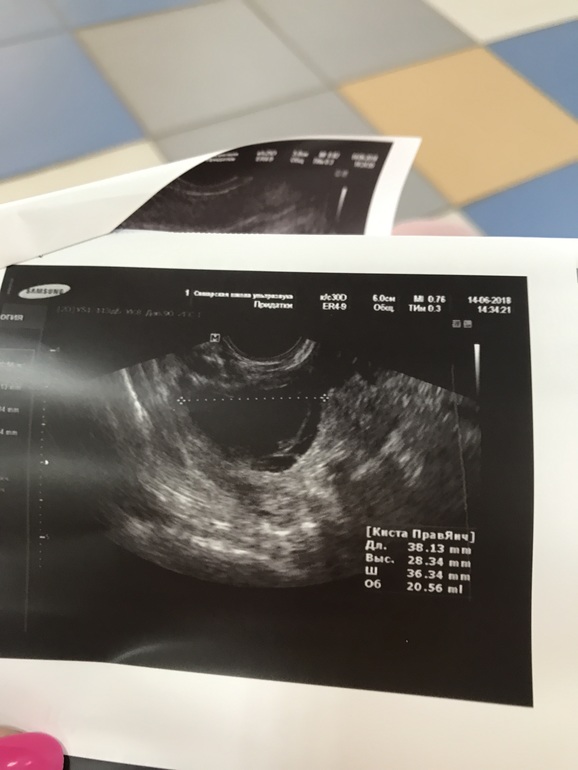

И вот сейчас 22 -й день цикла , была в отъезде , не было возможности делать УЗИ , делала тесты на овуляцию с 9 по 14 дц , но так и не дождалась положительного результата ( брала клеоблю - так и не дождалась улыбку )) не помню точно с какого дня , но неделю точно уже ( т.е с 15 дц ) начались боли в боках и слева и справа , но не прям где яичники , а выше .... эти боли мне прям дискомфорт доставляют ... усиливаются почему-то вечером тли прям когда спать ложусь 🤔 сегодня решила заехать на УЗИ глянуть что там ) и посмотреть была или не была овуляция .... и вот вышла и думаю , что лучше бы не заезжала ... одни неясности .. узитска ни на что не дала гарантий , все у неё под вопросом , и наставила кучу диагнозов 🤦♀️ Вышла вот вся в сметении и расстройствах , может кто разбирается и по фото может понять что и как ?